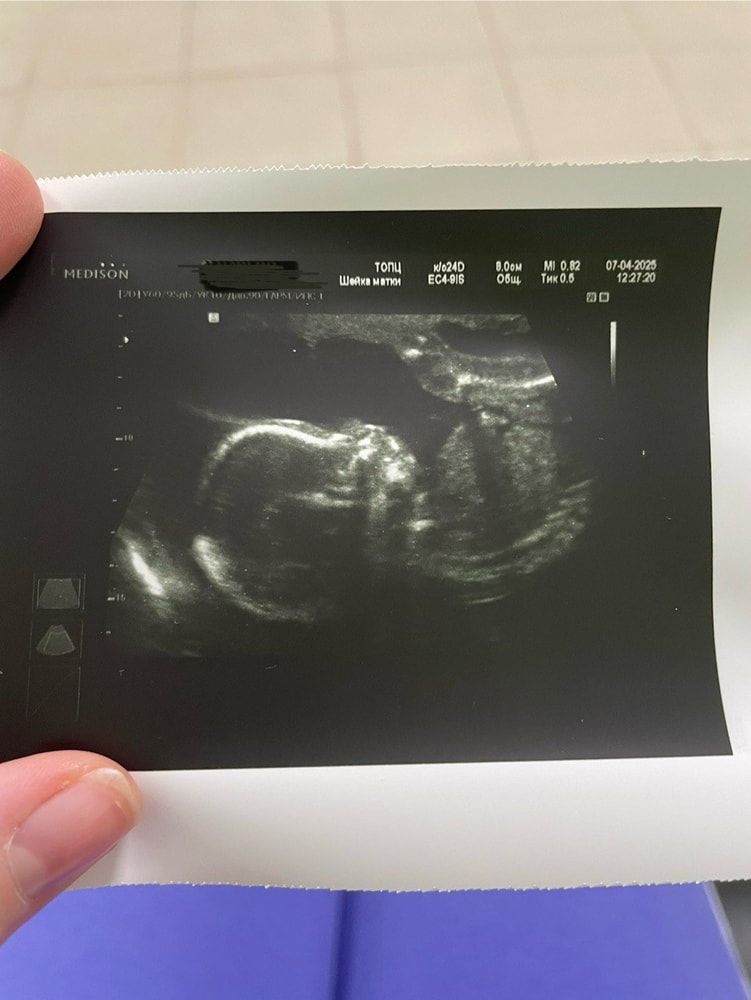

🧬7.04.25 - Второй скрининг (20нед 4 дн). Ну что - все классно! Все в порядке! Это подтвердил врач узи и после я еще заглянула к генетику, тоже сказала все риски низкие - все супер! Я счастлива! Про толчки спросила узистку - она показала на экране в момент толчков, дааа, я их все-таки 3 дня как чувствую! Получается первые нормальные отличимые толчки начались в 20+1 нед. После родов до 1 мес ребенка показать его генетику, направление дали. Просто чтобы вне утробы убедиться, что все в норме) Я не отказалась! Пусть посмотрят))

🧬Да, могу сказать, что узистка Москвина в перинаталке понравилась мне намного больше, чем Татарникова! Все показала, все рассказала. И даже фото дала (я не просила, зная, что в бесплатной не особо дают). Шейка 37мм. Норма. С утрика я слезла еще 2 апреля и безумно этому рада) На радостях от новостей я зашла в магазин и купила немного детских вещей) Так хочется уже наряжать своего ребенка. Гулять, читать ему, купать. Охото все-все показать и всему научить.

🧬Предположительно 375 грамм. Моя булка с маком)) Больше не опережает и не отстаёт. Сказали идет в середине норм таблиц. Количество вод - норма.